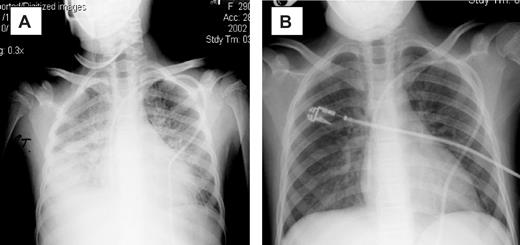

Clinical response

The introduction of etanercept was associated with a reduction in oxygen requirement in 13 patients, and in 10 patients a complete response (CR) to therapy was achieved (Table 2). Clearing of radiographic infiltrates accompanied clinical responses (Figure 1). The median time to CR was 7 days (range, 3-17 days), with a median of 2 etanercept doses (mean, 3 doses; range, 1-5 doses) required to achieve a CR. Two patients achieved CR after the first dose, and 4 achieved CR after the second dose of etanercept. Three of 8 (38%) patients on mechanical ventilation at initiation of etanercept therapy achieved a CR. Patients were more likely to have a CR if etanercept was started early after the onset of clinical IPS symptoms. For the 10 responding patients, therapy was initiated a median of 1 day from the diagnosis of IPS, compared with a median of 3 days in the 5 treatment failures. Although small numbers preclude statistical analysis, the 5 patients who did not achieve CR had a longer duration of severe symptoms (4 of 5 were mechanically ventilated ≥ 48 hours) at study entry.

Chest radiographs of patient 5. (A) Before therapy. (B) On therapy. Panel A was obtained on day 0 of study, with the patient requiring 100% FiO2 via bilevel positive airway pressure (BiPAP). Panel B was obtained 3 days later, with the patient now off all supplemental oxygen support.